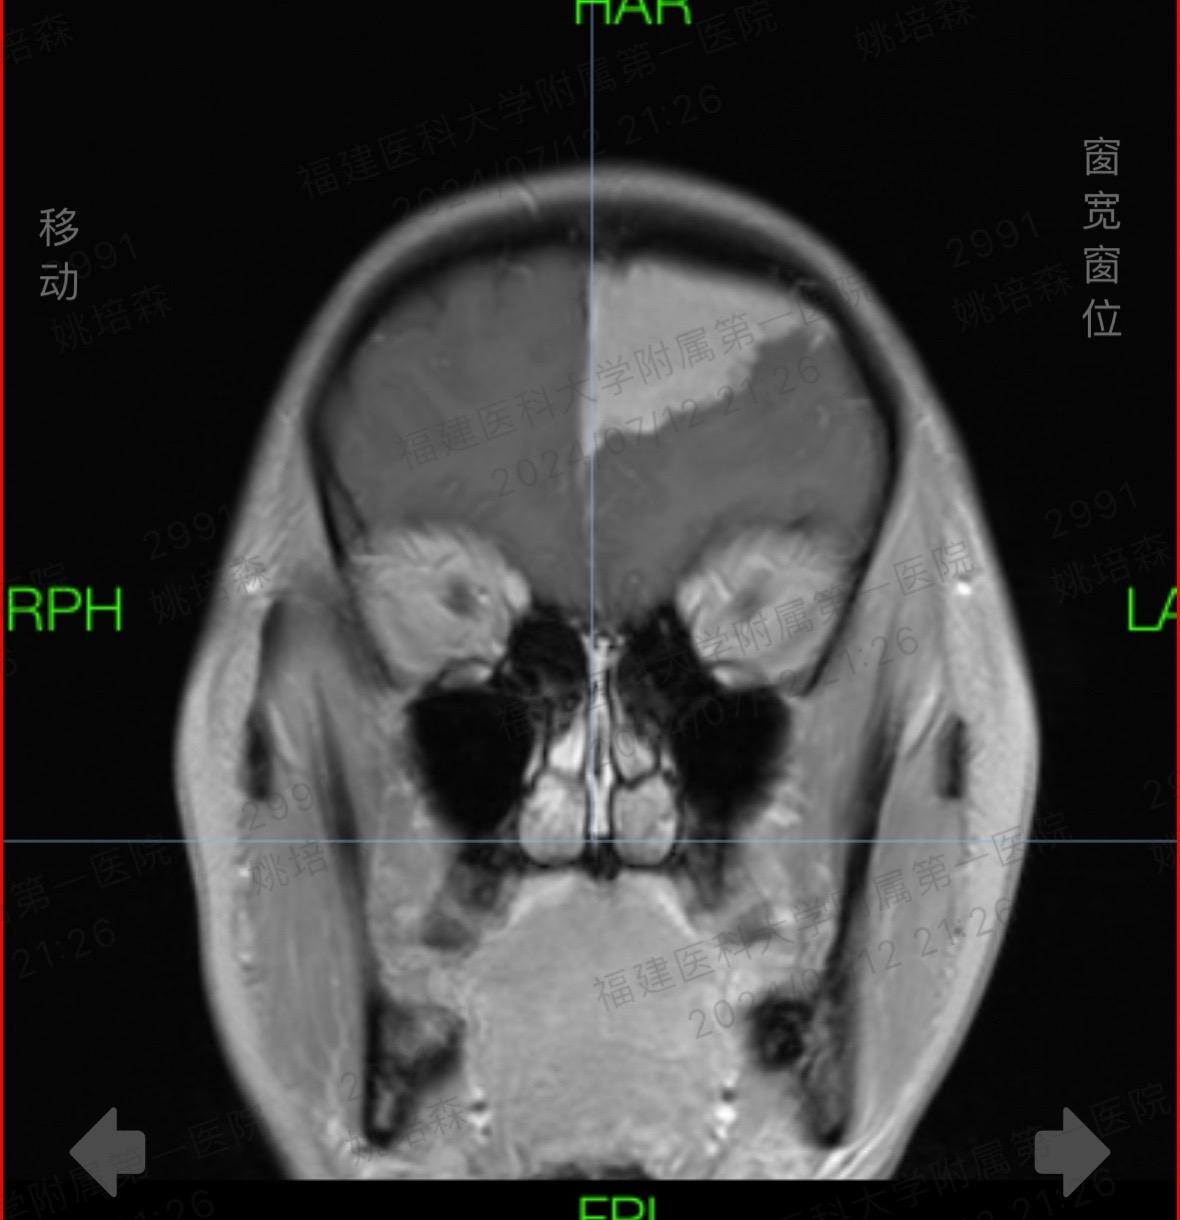

时光晃呀晃。连续10小时颅脑手术室日常 微创手术 手术,做了一台帕金森病,一台面肌痉挛,一台三叉神经痛,一台脑膜瘤,时光把我一整天晃走了,还让我累成了某某某!